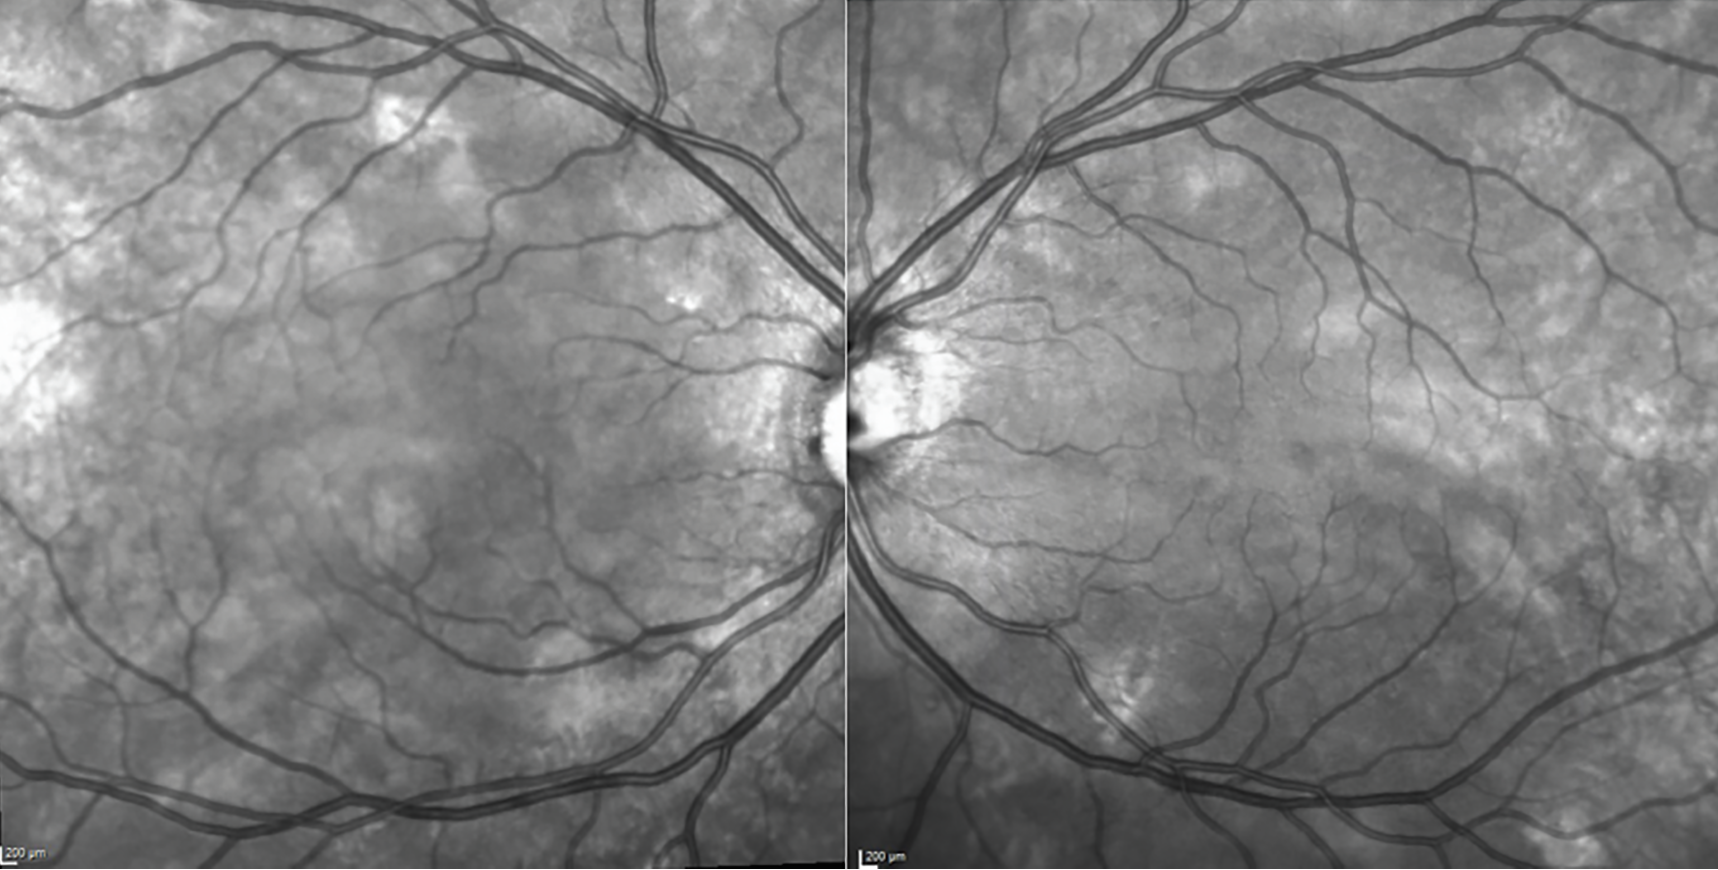

El ojo ha ganado protagonismo como una ventana al interior del funcionamiento del cerebro, debido a su origen embriológico compartido con el sistema nervioso central. Podemos utilizar ciertos biomarcadores para diagnosticar

mejor o prevenir estas condiciones neurodegenerativas.